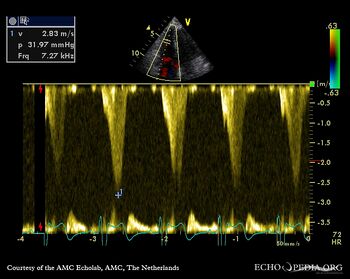

Double chambered right ventricle

A4CH with Color Doppler: high velocity signal in right ventricle Continuous-wave Doppler signal of gradient in right ventricle